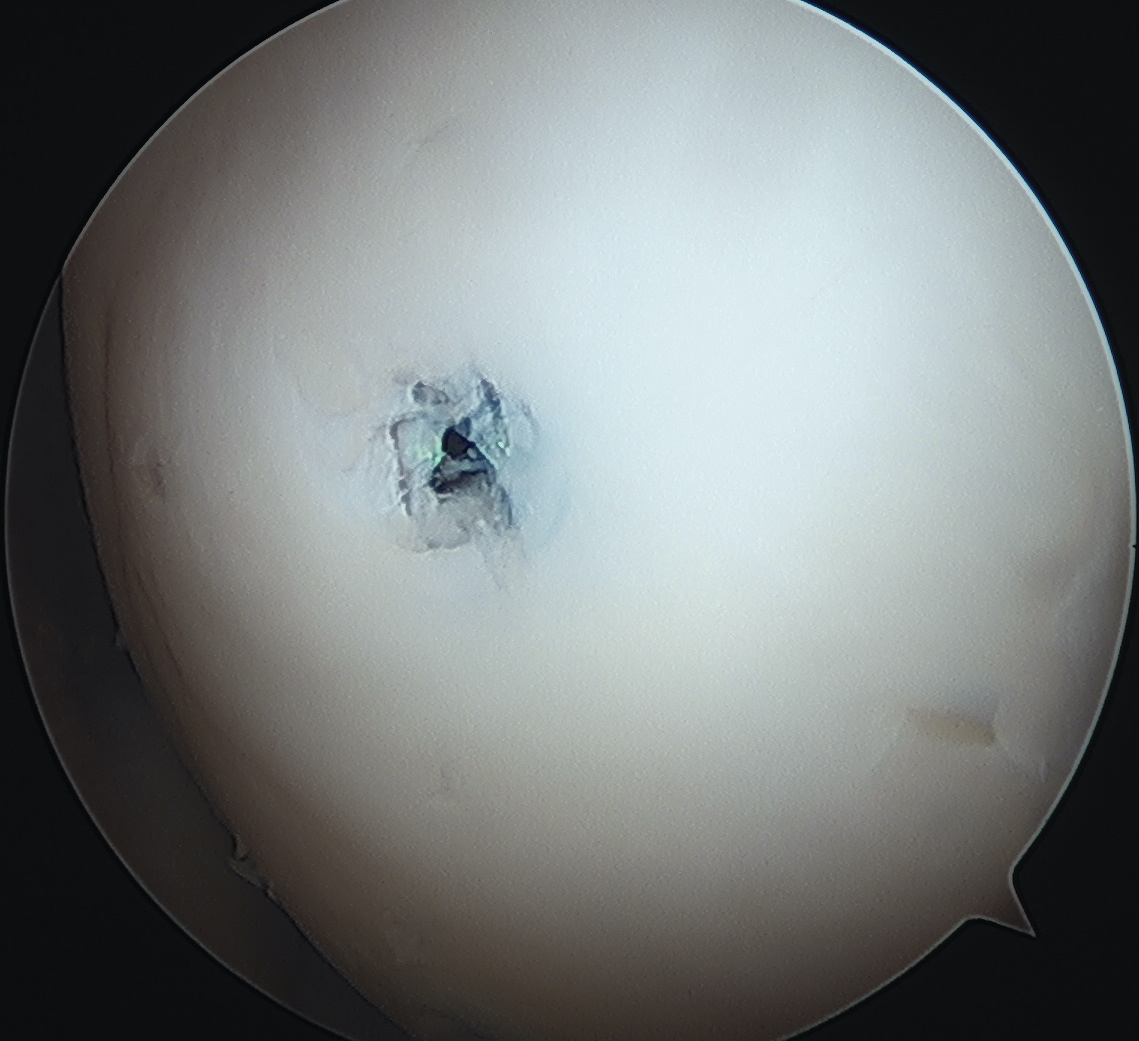

- ensure screw heads are buried under cartilage, but not too deep so they still engage fragment

- can microfracture with 1 mm k wire around screws